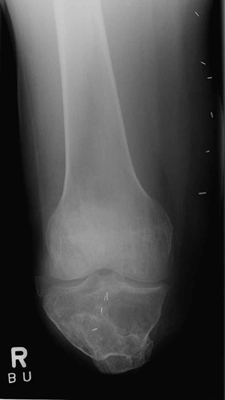

These images demonstrate a BKA that is too short to allow for use of a prosthesis.